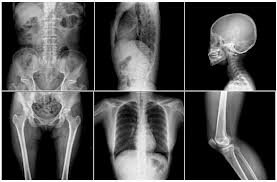

El uso más común de los rayos X es para ver fracturas, pero también se utilizan para otros usos. Por ejemplo, las radiografías de tórax pueden detectar neumonía. Esta relacionado con la prevención y tratamiento de enfermedades. Se invento en 1895.